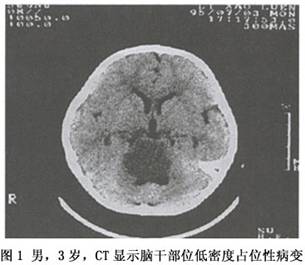

2.CT 表现为脑干部位的低或等密度占位(图1),也可为混杂密度,肿瘤多实性少囊变,不均匀强化。由于受后颅窝伪迹影响,肿瘤的显像效果不佳。 医学百科网 | YxBaike.Com